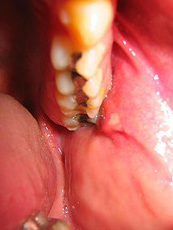

From above, we’ve established the important functions of saliva. All these functions are part of our saliva’s natural protective mechanism and if impaired, can cause oral health problems. There are two main aspects of saliva, the quantity and quality. When our salivary glands failed to produce adequate quantity of saliva, also known as hyposalivation, our mouths will become dry and unable to self-cleanse. And when our salivary glands failed to produce proper quality of saliva, our saliva will not be able to buffer acids effectively. These causes a whole strings of oral health problems, depending on the severity of the impairment. Common oral health problems arise from poor quantity and quality of saliva includes dental caries or tooth decay, halitosis or bad breath, and gingivitis or gum diseases. As stated in part 1 of the article, oral health is linked to our general health and in this case, lack of proper saliva can cause speech, chewing and swallowing difficulties. This is especially true in patients with dentures or plates that relies on saliva for retention and stability.